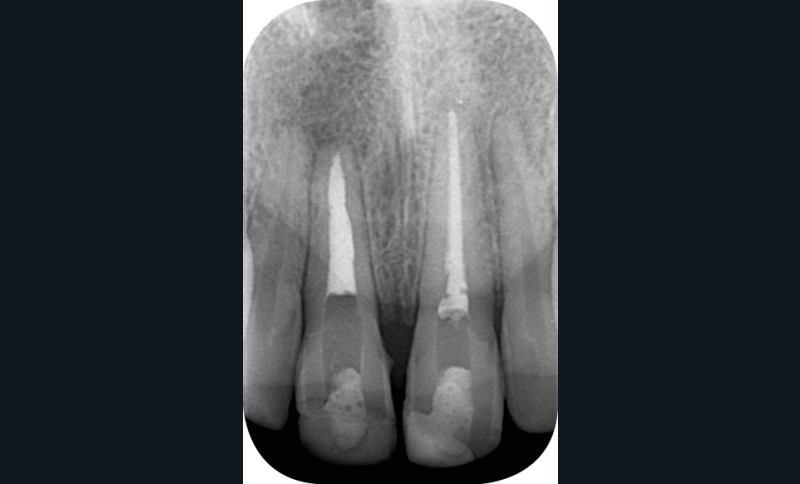

– les soins conservateurs et endodontiques [5] (fig. 4 et 5).

Les soins conservateurs et endodontiques sont majoritairement responsables des dyschromies des dents dépulpées. Nous allons développer ce point afin de mieux comprendre les paramètres régissant les colorations iatrogènes pour mieux les éviter et, si besoin, les corriger.

Ainsi, les ciments d’obturation canalaire sont la cause principale des dyschromies de la dent dépulpée [6]. Les modifications de couleur peuvent apparaître après une semaine seulement, lorsqu’il s’agit de ciments oxyde de zinc/eugénol (ZoE) [7, 8] ou à un mois post-traitement dans le cas de certaines biocéramiques [6].

Parmi les agents responsables de cette dyschromie, on peut citer l’eugénol, contenu dans les ciments ZoE et l’oxyde de bismuth, utilisé comme radio-opacifiant dans certaines biocéramiques, et principalement le MTATM [9]. L’oxyde de bismuth, quelle que soit sa concentration, même modérée dans le cas du MTA WhiteTM, provoque une coloration iatrogène de la dent en quelques semaines seulement [10] (fig. 6) [10]. Afin d’éviter ce type de dyschromies en secteur esthétique, il s’agit donc de privilégier dans notre pratique des biocéramiques qui contiennent un autre radio-opacifiant tel que l’oxyde de zirconium qui, lui, ne va pas créer de coloration iatrogène (BiodentineTM, TotallfillTM ou le BioRootTM) [11].